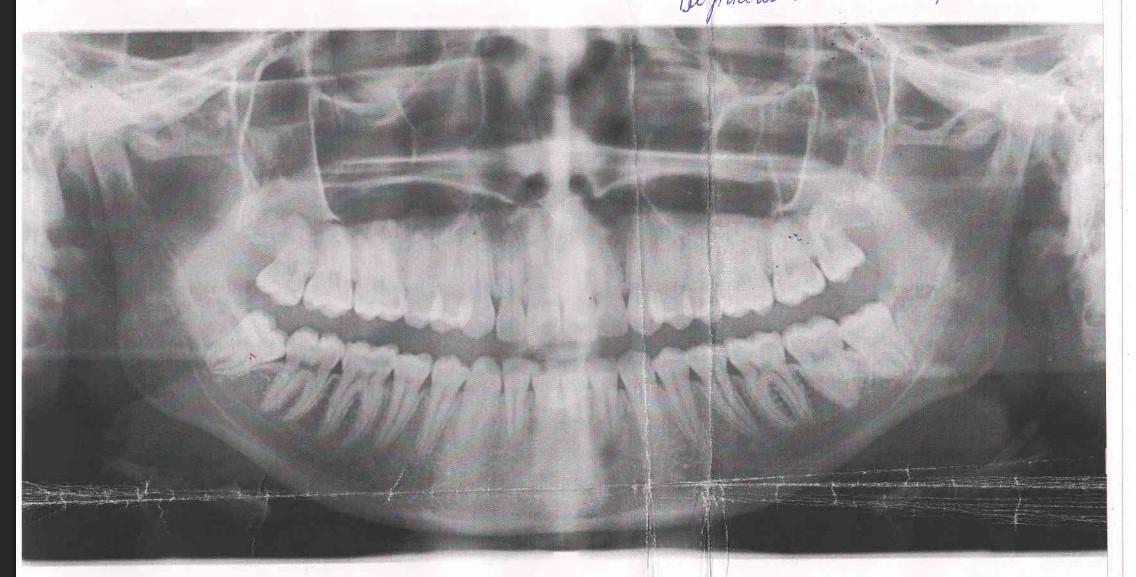

Здраствуйте. Выросли все 4 зуба мудрости почти незаметно за исключение правого нижнего, который сразу удалили, как стал беспокоить. Врач порекомендовал удалить все остальные. Левый нижний находится под капюшоном, верхние не беспокоят, но есть изменения в прикусе и улыбка стала будто уже (не знаю связано ли это с зубами мудрости). В чем вопрос, нужно ли удалять верхние зубы мудрости, если удалятся нижние (левый нижний скорее всего точно буду удалять, ибо как мне сказали он ретинированный и повреждает соседний 7-ой зуб)? Заранее спасибо за ответ.